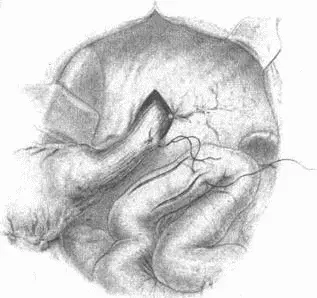

Рис. 78.Рассечение серозного покрова тонкой кишки, указывающего место наложения швов-держалок, и наложение первого шва на тощую кишку и пищевод